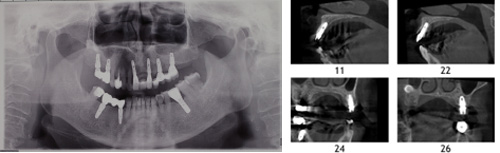

1.临床检查、数据采集与方案规划

利用专用的种植设计软件,通过CBCT 数据的三维重建,完成种植方案的规划设计。向患者详细介绍种植和修复方案,获得患者的认可。根据种植方案完成种植导板的数据模型,通过3D打印等技术完成种植导板的制作。如果种植方案为即刻修复,则根据种植导板完成临时修复体的制作。